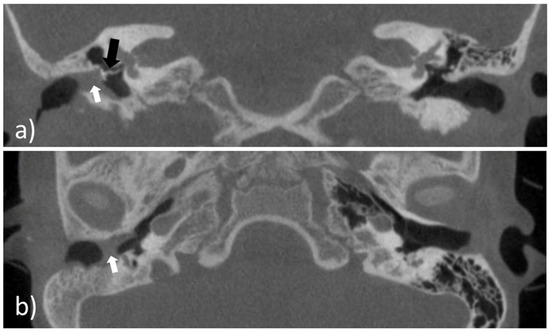

On the day of surgery, the patient underwent canaloplasty with removal of the restenosis on the right EEC under general anesthesia. Due to the patient history of three TM reconstructions a total reconstruction of the TM was performed using Tutoplast® Fascia lata and perichondrium. Then the EECI was inserted using forceps (Figure 8a,b) with ease. The distal end of the implant was placed with some distance to the tympanic ring and the proximal end rested on the opening of the EEC (Figure 8c).

Figure 8. Intraoperative images of the insertion of the 3D-printed, individualized, drug-releasing EECI. (a) After surgically removing the stenosis of the EEC, the EECI was inserted in the right position according to the patient’s anatomy; (b) the texture of the implant was deformable for better handling while insertion with the forceps; (c) perfectly fitted implant in the EEC of the patient.